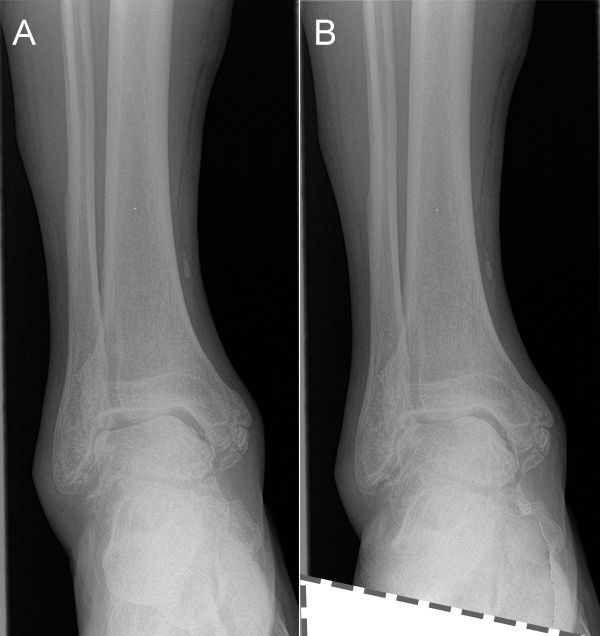

Native Röntgenaufnahmen des Sprunggelenks in 2 Ebenen unter Belastung (antero-posterior und lateral) erlauben Gelenkspaltverschmälerung, osteophytäre Anbauten sowie Achsfehlstellungen zu beurteilen. Eine „Canale-Aufnahme“ (Pronation des Fußes von ca. 15 °, Röntgenstrahl 75 ° nach kranial) 9 kann hilfreich sein, die subchondralen Oberflächen einzusehen. Die korrekte Abbildung der Sprunggelenkgabel in der sogenannten „Gabel-Aufnahme“ (mortise-view) ist zudem notwendig zur Beurteilung der Gelenkkongruenz. An Grenzen stößt die konventionelle Röntgenaufnahme allerdings bei OCLs ohne weitere knöcherne Veränderungen. Bis zu 50% der OCLs sind auf konventionellen Röntgenaufnahmen nicht sichtbar. Auch kann der Zustand des Knorpels nicht beurteilt werden 10. Bei Achsfehlstellungen werden zusätzlich Rückfußachs-Aufnahmen (Saltzman View) angefertigt bzw. eine Einbeinstandaufnahme zur Bestimmung der Becken-Bein-Achse.